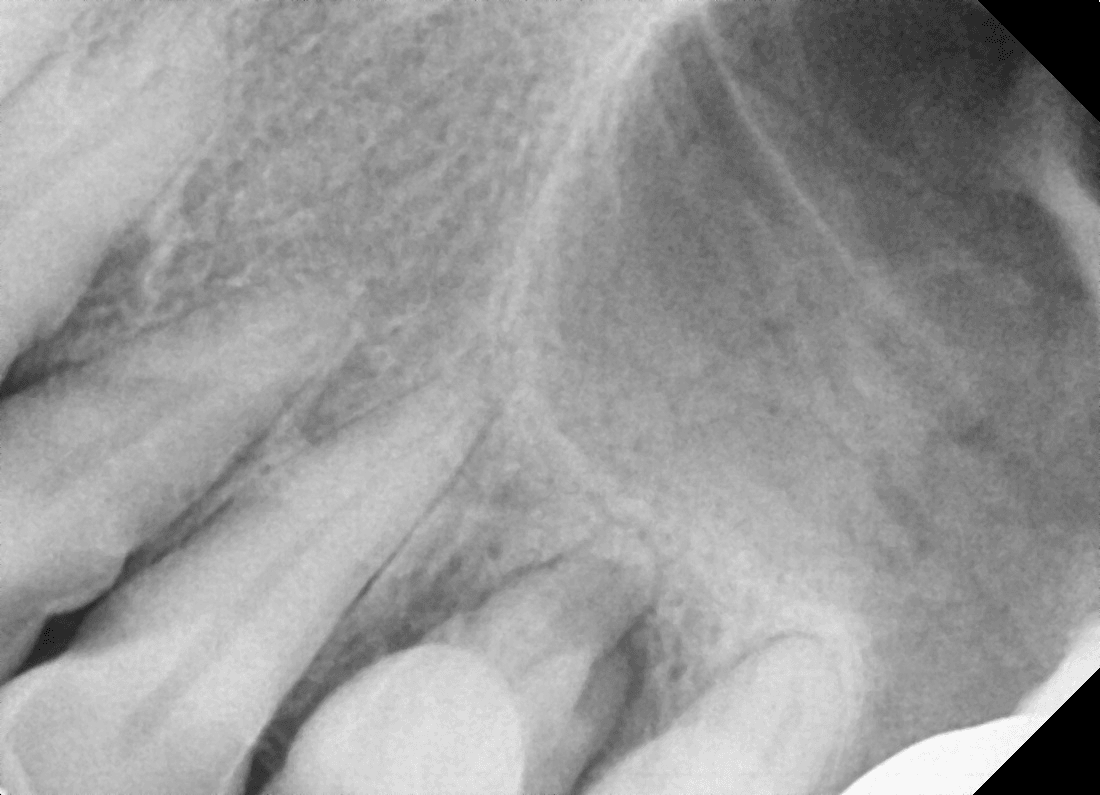

신경치료 후 통증은 왜 더 아픈가요? (서면 40대 중반/여 신경치료 후 통증)

신경치료를 했는데 오히려 치료 전보다 더 아픈 느낌이 들어요.

치료가 잘못된 건가요?

신경치료 후 통증은 비교적 흔하게 나타날 수 있는 반응입니다.

신경을 제거하는 과정에서

치아 뿌리 끝 조직이 자극을 받기 때문에

며칠간 욱신거리거나 씹을 때 통증이 느껴질 수 있습니다.

대부분은 시간이 지나면서 점차 호전되지만,

통증이 심해지거나 오래 지속된다면

뿌리 끝 염증, 교합이 높은 경우, 잔존 염증 등이 원인일 수 있습니다.

이럴 경우에는 참지 말고

치과에 내원해 교합 조정이나 추가 치료가 필요합니다.